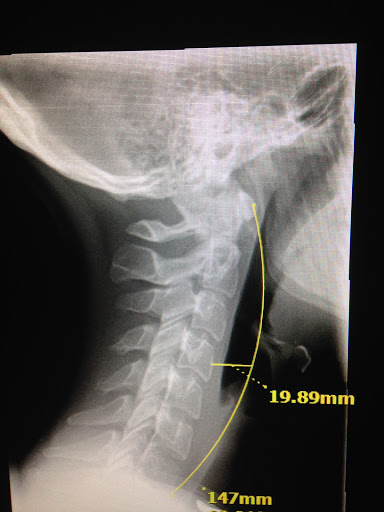

I was in such severe pain when I found Dr. Allen, I really had lost hope in living a full happy life as my pain had become unmanageable. Dr. Allens gentle, confident, holistic, well trained whole body approach in dealing with my severe pain from injured lumbar and neck, saved me from intense daily pain. Through his use of very customized gentle specific maneuvers to realign my scoliotic spine and neck, and with his laser treatments, I now can enjoy life without surgery and movement without debilitating pain. Being pain free is a miracle I can attribute to Dr. Allen. Thank you so much. You are blessed and gifted beyond your education and training!!! Susie Jerome, PsyD.